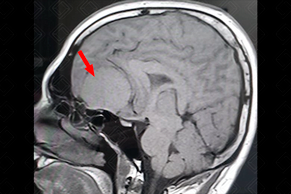

Texto alternativo para a imagem Figura 1. Créditos: Dra. Elazir Mota - Rio de Janeiro/RJ

Descrição da figura 1: Ressonância magnética T1, evidenciando lesão expansiva suprasselar, com sinal isointenso na sequência T1.